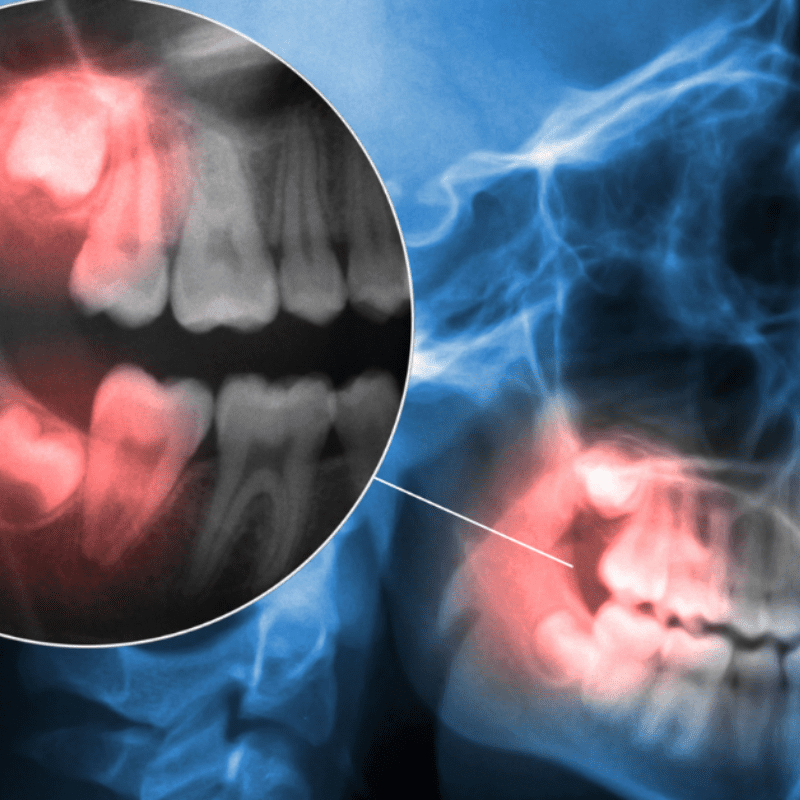

Wisdom teeth are the third and final set of molars that come in, usually between the ages of 17 and 25. As adult teeth naturally only come with 32 slots, when the 32nd tooth arrives, there isn’t always enough room for it, causing what is known as “impaction.”

If left untreated, neglected, impacted wisdom teeth can lead to a variety of dental problems and even other issues like misalignment of other teeth. However, by having them removed, you could reap several oral health benefits!

Having impacted wisdom teeth can lead to misaligning other teeth in your mouth, which can cause difficulty when you’re trying to bite down and chew. Having them removed will help keep the alignment of your other teeth intact so that way you have an easier time eating and speaking.

Impacted wisdom teeth can put pressure on other teeth and the jaw, causing discomfort. Wisdom teeth eruption can also cause swelling and inflammation of the gums. Removing them can help alleviate any orofacial pain or extreme discomfort you may be experiencing.